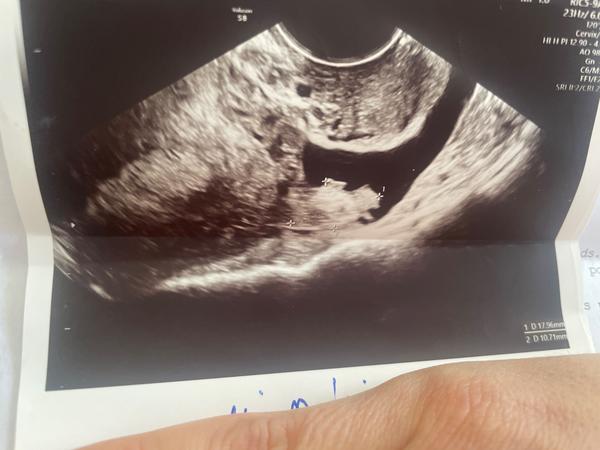

Dobrý deň, vyšiel mi pozit. Test takze som bola doktorkou privolaná na usg nakoľko je to 2 mesiace po kyrete pre MA. Hcg mi vyšlo 160 čo je vraj vramci štádia tehotnosti v poriadku. Na usg však plodový vak ešte vidieť nebolo, ale videla tam z pravého vsjecnika žlté teliesko, kt vraj o tehotnosti svedčí. Endometrium 14. Problém však nastáva že na ľavej strane našla nejaký útvar vraj asi cysta a aj tekutinu, podľa nej nie krv ale nejaká tekutina. Nevedela identifikovať . Čítam doma správu a ona tam dala diagnózu v úvodzovkách molarne tehotenstvo s popisom pravý vaječníka cystickaa štruktúra 42x23mm a ľavý vaječník pri okraji nehomogénnu štruktúra 18x10mm bez navigácie. Čo to teda môže znamenať ? :( o dva dni mám ísť na usg asi aj kontrolu hcg no ten nález nie je “pekne napísaný” ale ústne sa nevyjadrila nijak záporne … povedala len že radšej byt obozretný . Vraj to čo je vľavo na vajecniku mohlo byt aj to že aj z tohto vsjecnika sa uvoľnilo vajíčko čo môže signalizovať aj mimomaternicove… už som toho total zmätená a neviem čo si myslieť. Máte niektorá skúsenosti ? Prikladám usg vaječníkov

Fu no, tehotenstvo na sone je vidieť keď je hcg nad 1000. Mala by ro vziať krv o 2dni či hcg narástlo raz toľko. Na sone sa toho moc nezmení (s cystami ale skúsenosť nemám)